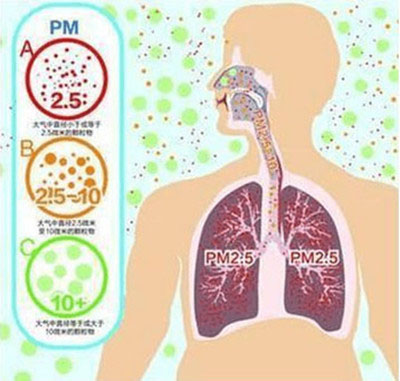

像沙尘暴,它属於PM10级别的颗粒,人体可以通过打喷嚏丶流鼻涕丶咳嗽等方式排出体外。但PM2.5颗粒物,人体的咽喉已经无法阻挡,它可以一路下行,直至肺泡。尤其PM2.5像是一个载体,承载着含有氮氧化物丶硫酸盐丶病毒等有害物质,这些停留在肺泡的毒颗粒,最终会影响我们的上皮组织,使抑癌基因失活,诱发肺癌。

PM是英文Particulatematter颗粒物的缩写,2.5则表示这种颗粒物的直径。颗粒物一般分为两类:PM2.5和PM10。 PM2.5是指直径小於或等於2.5微米的颗粒物,相当於头发丝直径的1/20,已到达肺泡的临界值。 PM2.5以下的细微颗粒物,人体的鼻腔丶咽喉已经挡不住,它们可以一路下行,进入细支气管丶肺泡,再通过肺泡壁进入毛细血管,再进入整个血液循环系统。对人体的呼吸系统和心血管系统造成伤害。

1丶呼吸系统

众所周知,PM2.5对人体最直接丶影响最大的莫过於对呼吸系统造成的伤害了。 PM2.5以下的细微颗粒物,人体的鼻腔丶咽喉已经挡不住,它们可以一路下行,进入细支气管丶肺泡,再通过肺泡壁进入毛细血管,再进入整个血液循环系统。

PM2.5像是一个载体,携带了许多有害物质,如细菌丶致癌物多环芳烃丶重金属等。大量的颗粒物进入肺部对局部组织有堵塞作用,可使局部支气管的通气作用下降。我们可以想像,眼睛里进了沙子,眼睛会发炎。呼吸系统的深处,也是一个敏感环境,细颗粒物作为异物长期停留在呼吸系统内,同样会让呼吸系统发炎。造成咳嗽丶呼吸困难丶鼻炎咽炎丶加重哮喘丶导致慢性支气管炎等。